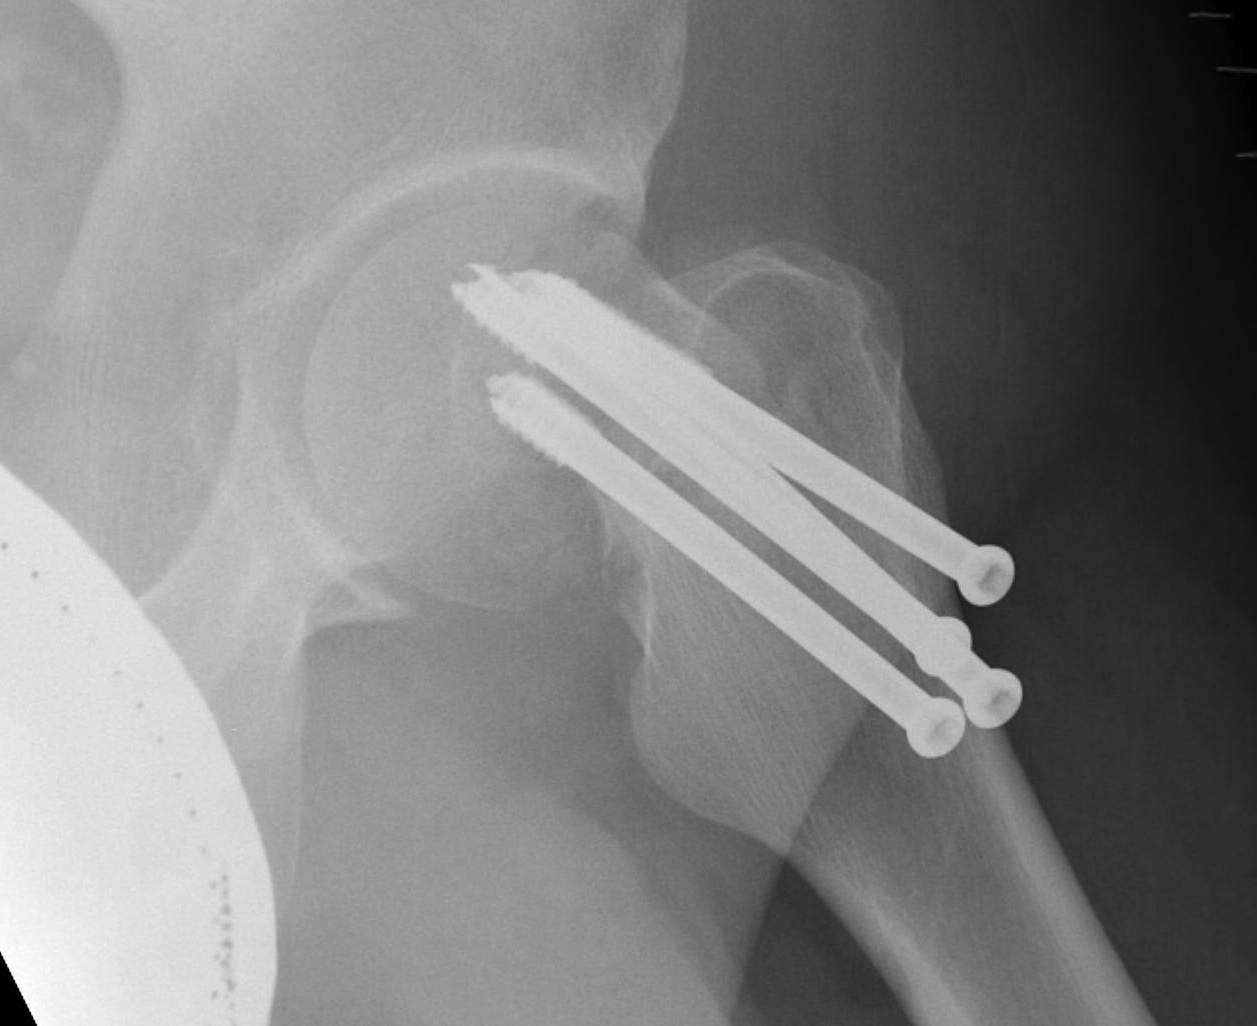

Cannulated screws

Technique

- 3 screws

- ensure inferior screw entry point is above lesser trochanter to prevent fracture

- ensure threads cross fracture site entirely to obtain compression

- need correct screw length so screw head can compress against cortex